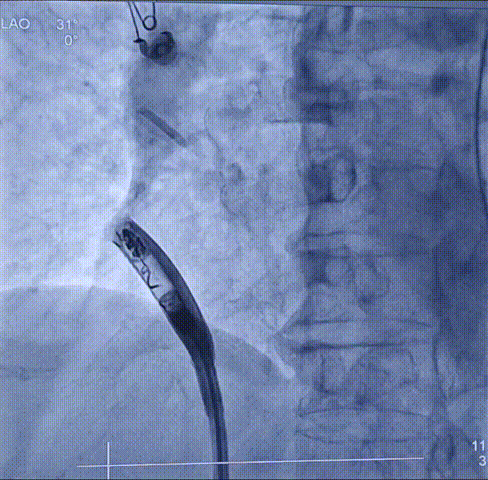

左右前斜造影图

手术过程十分顺利,手术团队通过精细、精准的操作,将仅有传统起搏器十分之一大小的新型无导线起搏器输送至右心耳,利用其特有的用于心房起搏的双螺旋设计,起搏器被牢固地锚定在右心耳基底部。整个手术过程顺利,耗时仅约30分钟,术中及术后参数测试均十分优异、显示起搏器工作状态良好。